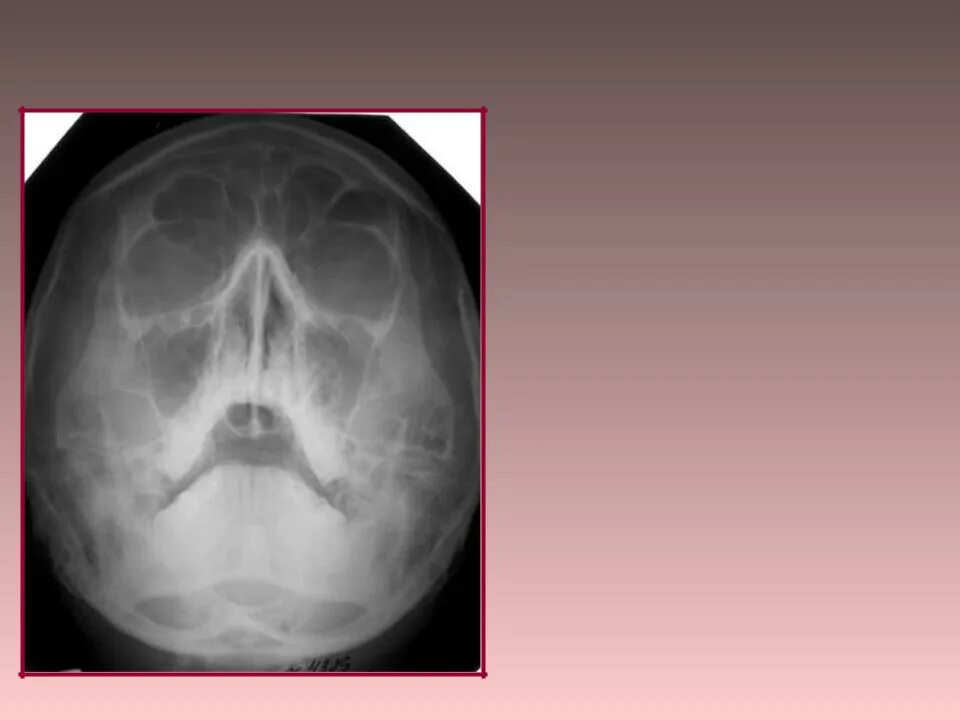

Снимок в прямой проекции